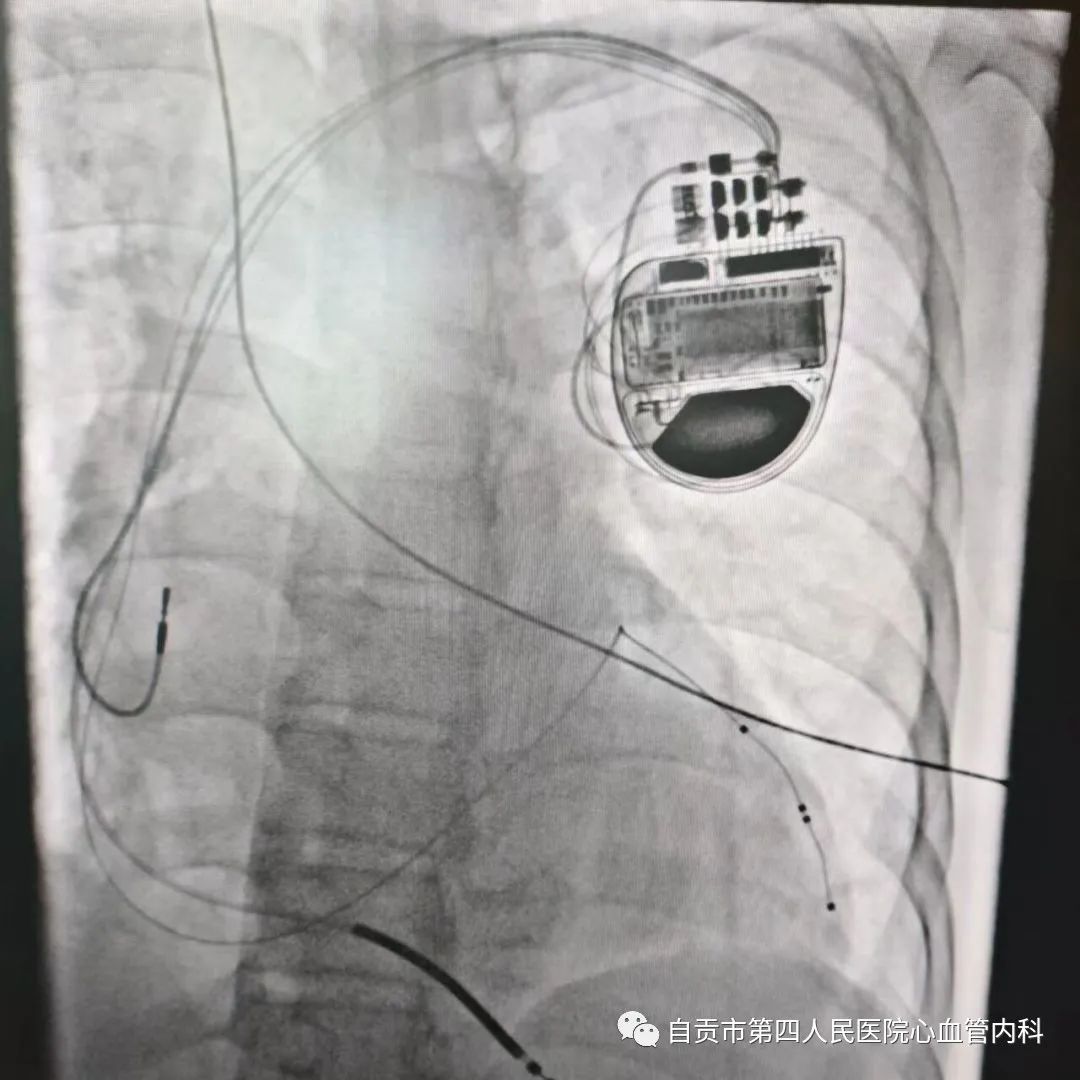

2023年7月16日,自贡市第四人民医院心血管内科介入团队在罗裕主任领导下荣幸邀请到上海同济大学附属东方医院大咖浦介麟教授来院授课,并在教授指导下成功为一位扩张型心肌病患者顺利植入了一个三腔起搏器(CRT-D),让患者衰竭的心脏重获新生,该手术技术难度大,省内仅有较大的心脏中心开展,手术的成功标志着我院心内科在心脏起搏治疗领域又迈上了新台阶。

术中浦教授主刀,在心内科团队的密切合作下,手术顺利完成,术后患者恢复良好。

三腔起搏器(心脏再同步除颤器)是目前治疗心衰最有效的方法之一,但该手术技术难度大,手术操作要求高,传统起搏器的植入主要通过静脉穿刺输送两根电极分别植入右心房、右心室即可,三腔起搏器第三根电极要求植入的位置是左心室,常规通过冠状静脉窦逆行至心脏侧静脉植入左室电极,极大的增加手术难度及风险,全国在心脏大中心开展稍多,省内地市级医院鲜有开展,该项手术的成功开展为心衰患者带来新的希望,同时标志着我院起搏技术及心衰治疗水平的走在全省前列。